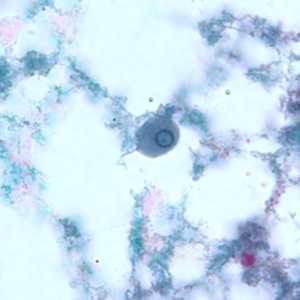

Figure A: Cysts of E. nana stained with trichrome.

Figure B: Cyst of E. nana stained with trichrome.

Figure C: Cyst of E. nana stained with trichrome.

Figure D: Cyst of E. nana stained with trichrome.